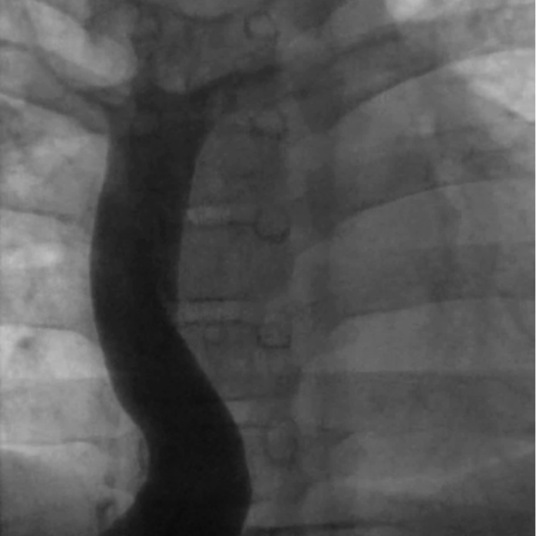

肺動脈閉鎖症,無脾症の診断で月齢3に左BTシャント変法を施行された.シャント閉塞認め,1歳3か月時に左BTシャント変法を,2歳時に右BTシャント変法を追加された.3歳時に両方向性グレン手術施行し,5歳時に心外導管型フォンタン手術(ePTFE 18 mm)施行した.術直後の心臓カテーテル検査から心外導管に造影欠損部を認めており,2 mmHgの圧較差を認めていた(Fig. 5). 17歳時の心臓カテーテル検査では,心外導管の圧較差2 mmHgと狭窄の進行はなく,下大静脈圧は14 mmHgで再手術の適応はないと判断されていた.17歳ごろより1年間ワーファリンを自己中断していた.その後当院成人先天性心疾患外来紹介.19歳時より倦怠感,下血,喀血が出現し,心臓カテーテル検査を施行した.下大静脈圧は26 mmHg,平均肺動脈圧は8 mmHgと圧較差を14 mmHg認めた(Fig. 6),心外導管に対してバルーン拡張術を施行し,下大静脈圧は20 mmHgと軽度改善したが下大静脈圧の十分な低下は得られず,手術適応と考えられ,再心外導管置換目的に当科入院となった.

Fig. 6 Preoperative angiography showing severe stenosis and a high number of collateral vessels in patient 2